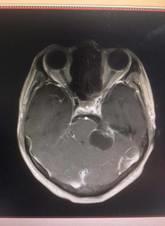

术前 术后

神经外科完成的两例听神经瘤手术中肿瘤位置在颅脑深部的桥小脑角区,该区域与负责我们人体的听力、面部感觉、闭眼活动、发声、吞咽、耸肩等活动相关的颅神经关系十分紧密,与面神经粘连在一起,特别是还与号称“外科手术禁区”和“生命中枢”所在的脑干紧密粘连,手术既要尽量全切肿瘤又要保护以上重要神经和结构,加之患者高龄,肿瘤体积大,手术风险和难度较普通听神经瘤手术高的多。